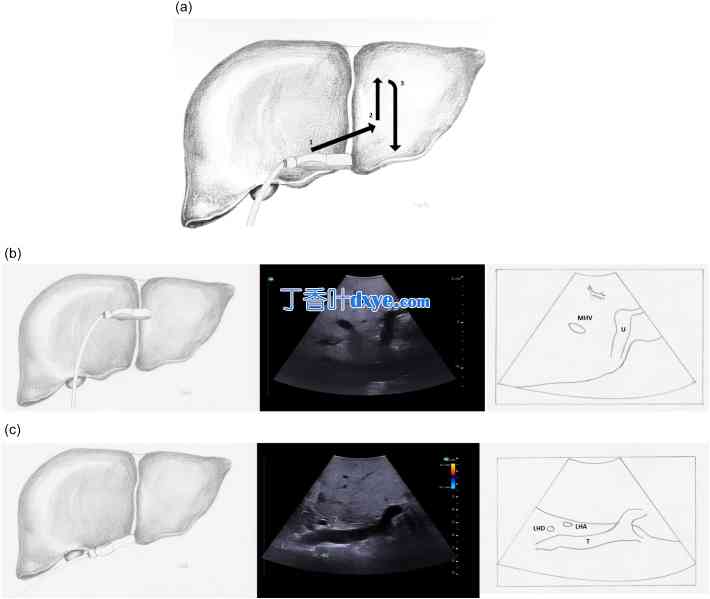

图 18

术中左门静脉超声检查。a) 箭头表示超声探头应移动的方向,同时保持横向方向,以观察左门静脉的分段分支,b) 左门静脉的脐部,c) 左门静脉的横向部分。

LHD 左肝管,LHA 左肝动脉,MHV 中肝静脉,U 左门静脉的脐部,T 左门静脉的横向部分。